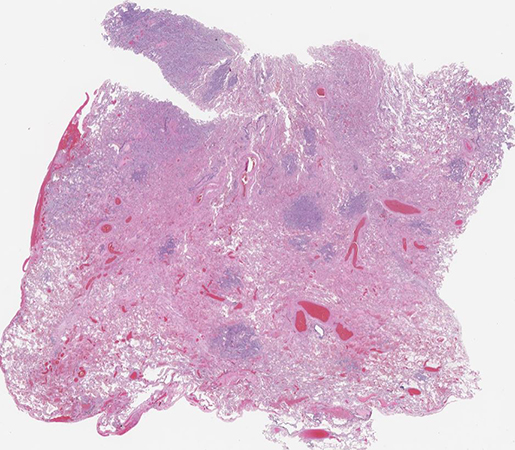

Clinical History: A 77-year-old man, heavy smoker, with history of chronic obstructive pulmonary disease with severe paraseptal emphysema, and recurrent pneumothoraces, who presented with cough and inspiratory chest pain, and was found to have a moderate left pneumothorax with a left upper lobe (LUL) consolidation. A LUL wedge resection was performed showing prominent multifocal micronodular epithelial cell proliferation (Figures 1-3). Immunohistochemical stains (IHC) showed the neoplastic cells to be positive for pancytokeratin (AE1/AE3), WT1, and calretinin (Figure 4), but negative for claudin-4, CEA, TTF-1, p40, CD163, S100, CD1a, ERG, CD31, SOX10, SMA and collagen IV. BAP1 expression was lost by IHC (Figure 5), and several asbestos bodies were identified on an iron stain (Figure 6).

Histology is characterized by multinodular proliferation of mildly atypical epithelioid cells with a variety of growth patterns mimicking adenocarcinoma, including lepidic, acinar, solid and micropapillary. Cytologically, the tumor cells are cuboidal and enlarged, and contain moderate eosinophilic or amphophilic cytoplasm with frequent prominent single central nucleoli. Lymphovascular invasion and lymph node metastases may be present. DIM can mimic a broad variety of conditions, with some cases having been described as morphologically similar to desquamative interstitial pneumonia, organizing pneumonia, pneumoconiosis, hypersensitivity pneumonitis, or Langerhans cell histiocytosis (Question 2).